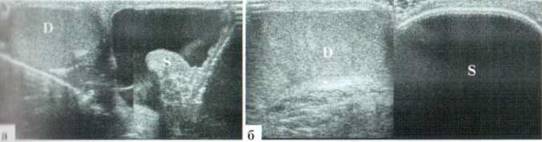

Рис. 2.1.2. Крупные размеры трансформированной гидатиды: 1 — яичко, 2 — гидатида. Размеры яичка и гидатиды практически одинаковы. Сосудистый рисунок при ДДС в гидатиде не прослеживается (б)

Частыми осложнениями трансформации гидатиды являются эпидидимит и реактивный выпот в оболочках яичка. Придаток яичка при этом значительно увеличивается в размерах, и при допплеровском исследовании определяется значительное усиление в нем сосудистого рисунка. Выпота в оболочках яичка обычно бывает немного (рис. 2.1.3). Также в большинстве случаев эхографически определяется утолщение мягких тканей мошонки на стороне поражения за счет выраженного отека.

Рис. 2.1.3. Трансформация гидатиды, реактивный эпидидимит: 1 — яичко; 2 — увеличенный в размерах, гиперемированный придаток; 3 — трансформированная гидатида; 4 — выпот в оболочках; 5 — значительно утолщенные мягкие ткани мошонки